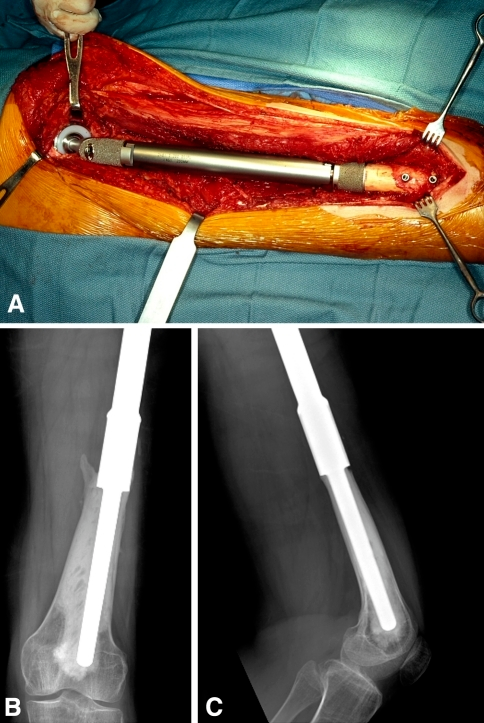

Prótesis cementada / Cemented prosthesis

Prótesis cementada

Cemented prosthesis

Prótesis que implican la utilización de cemento acrílico de polimetilmetacrilato como método de anclaje o fijación de los componentes.

A cemented prosthesis is a lower-modulus device because the cross section is reduced as an intervening layer of cement is interposed between the cortex and the metallic stem.